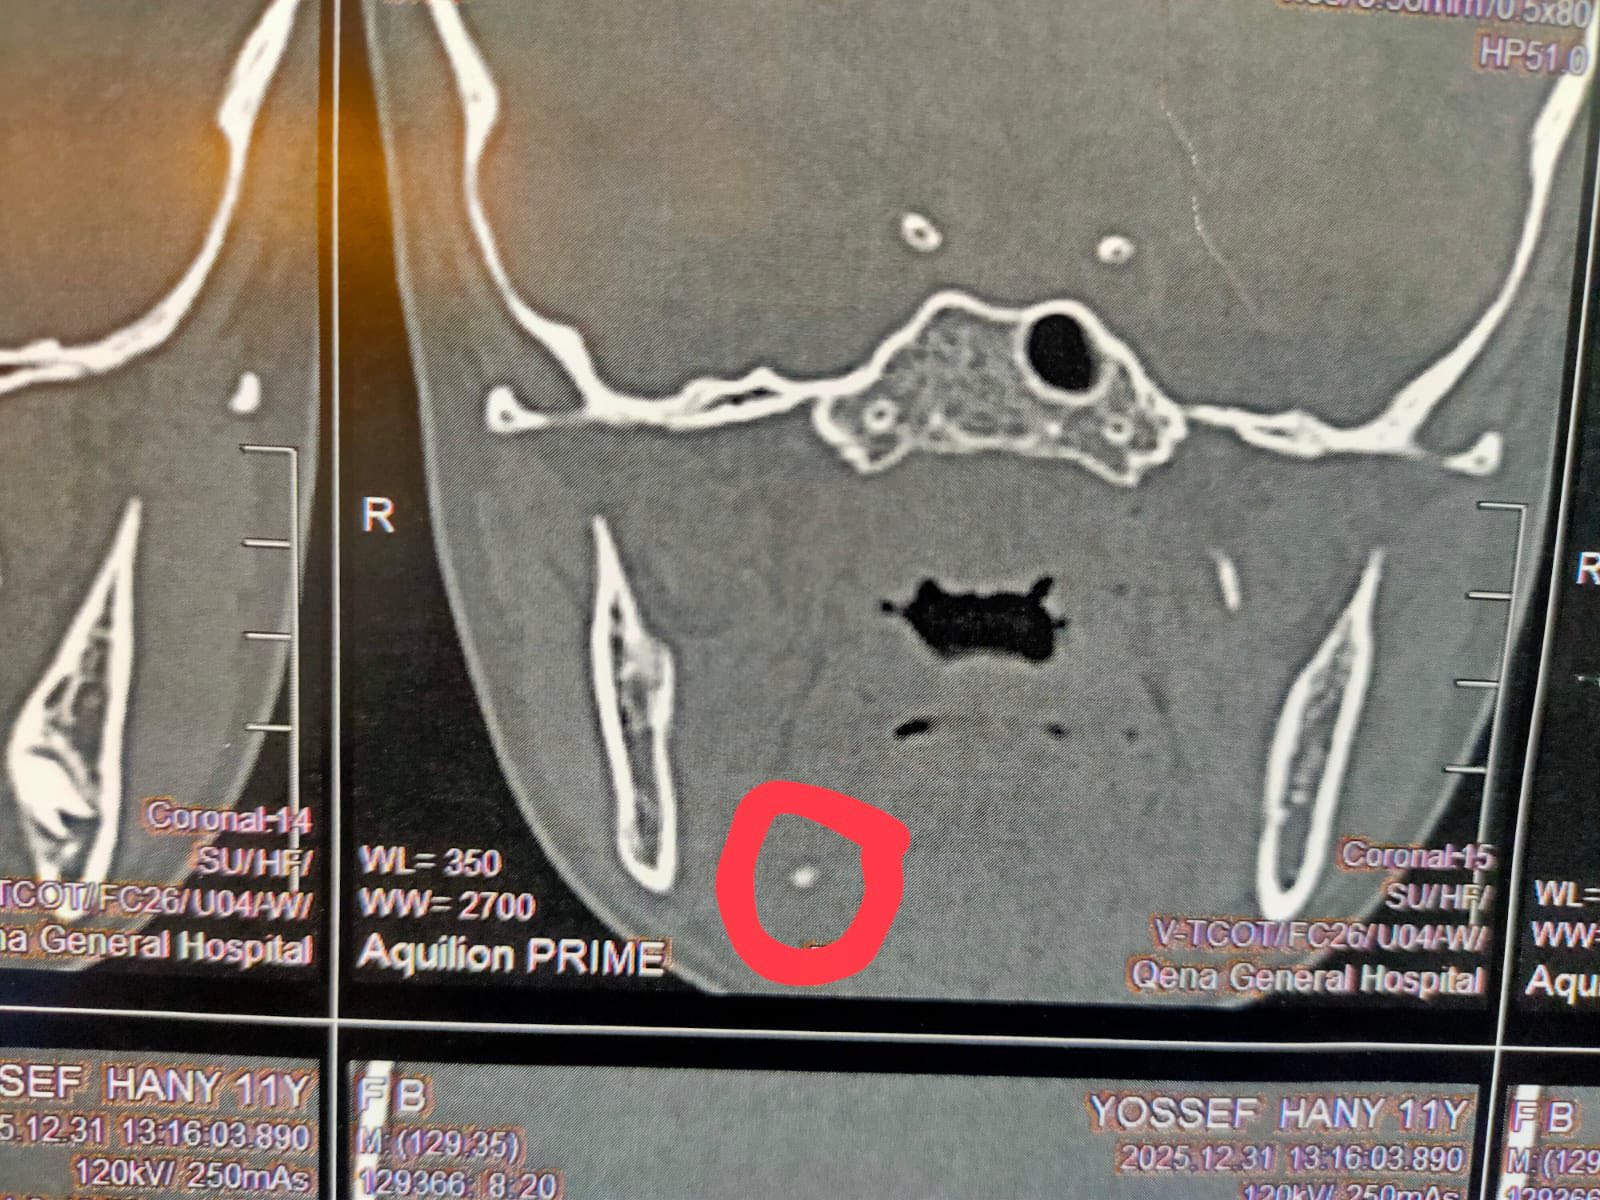

أعلن مستشفي قنا العام ، عن نجاح فريق طبي ، في إجراء جراحة عاجلة لطفل يبلغ من العمر 11 عامًا كان يعاني من تورم متكرر بالناحية اليمنى من الفكـ ، وبعد توقيع الكشف الطبي وإجراء الأشعة المقطعية اللازمة، تبيّن وجود حصوة بالغدة اللعابية.